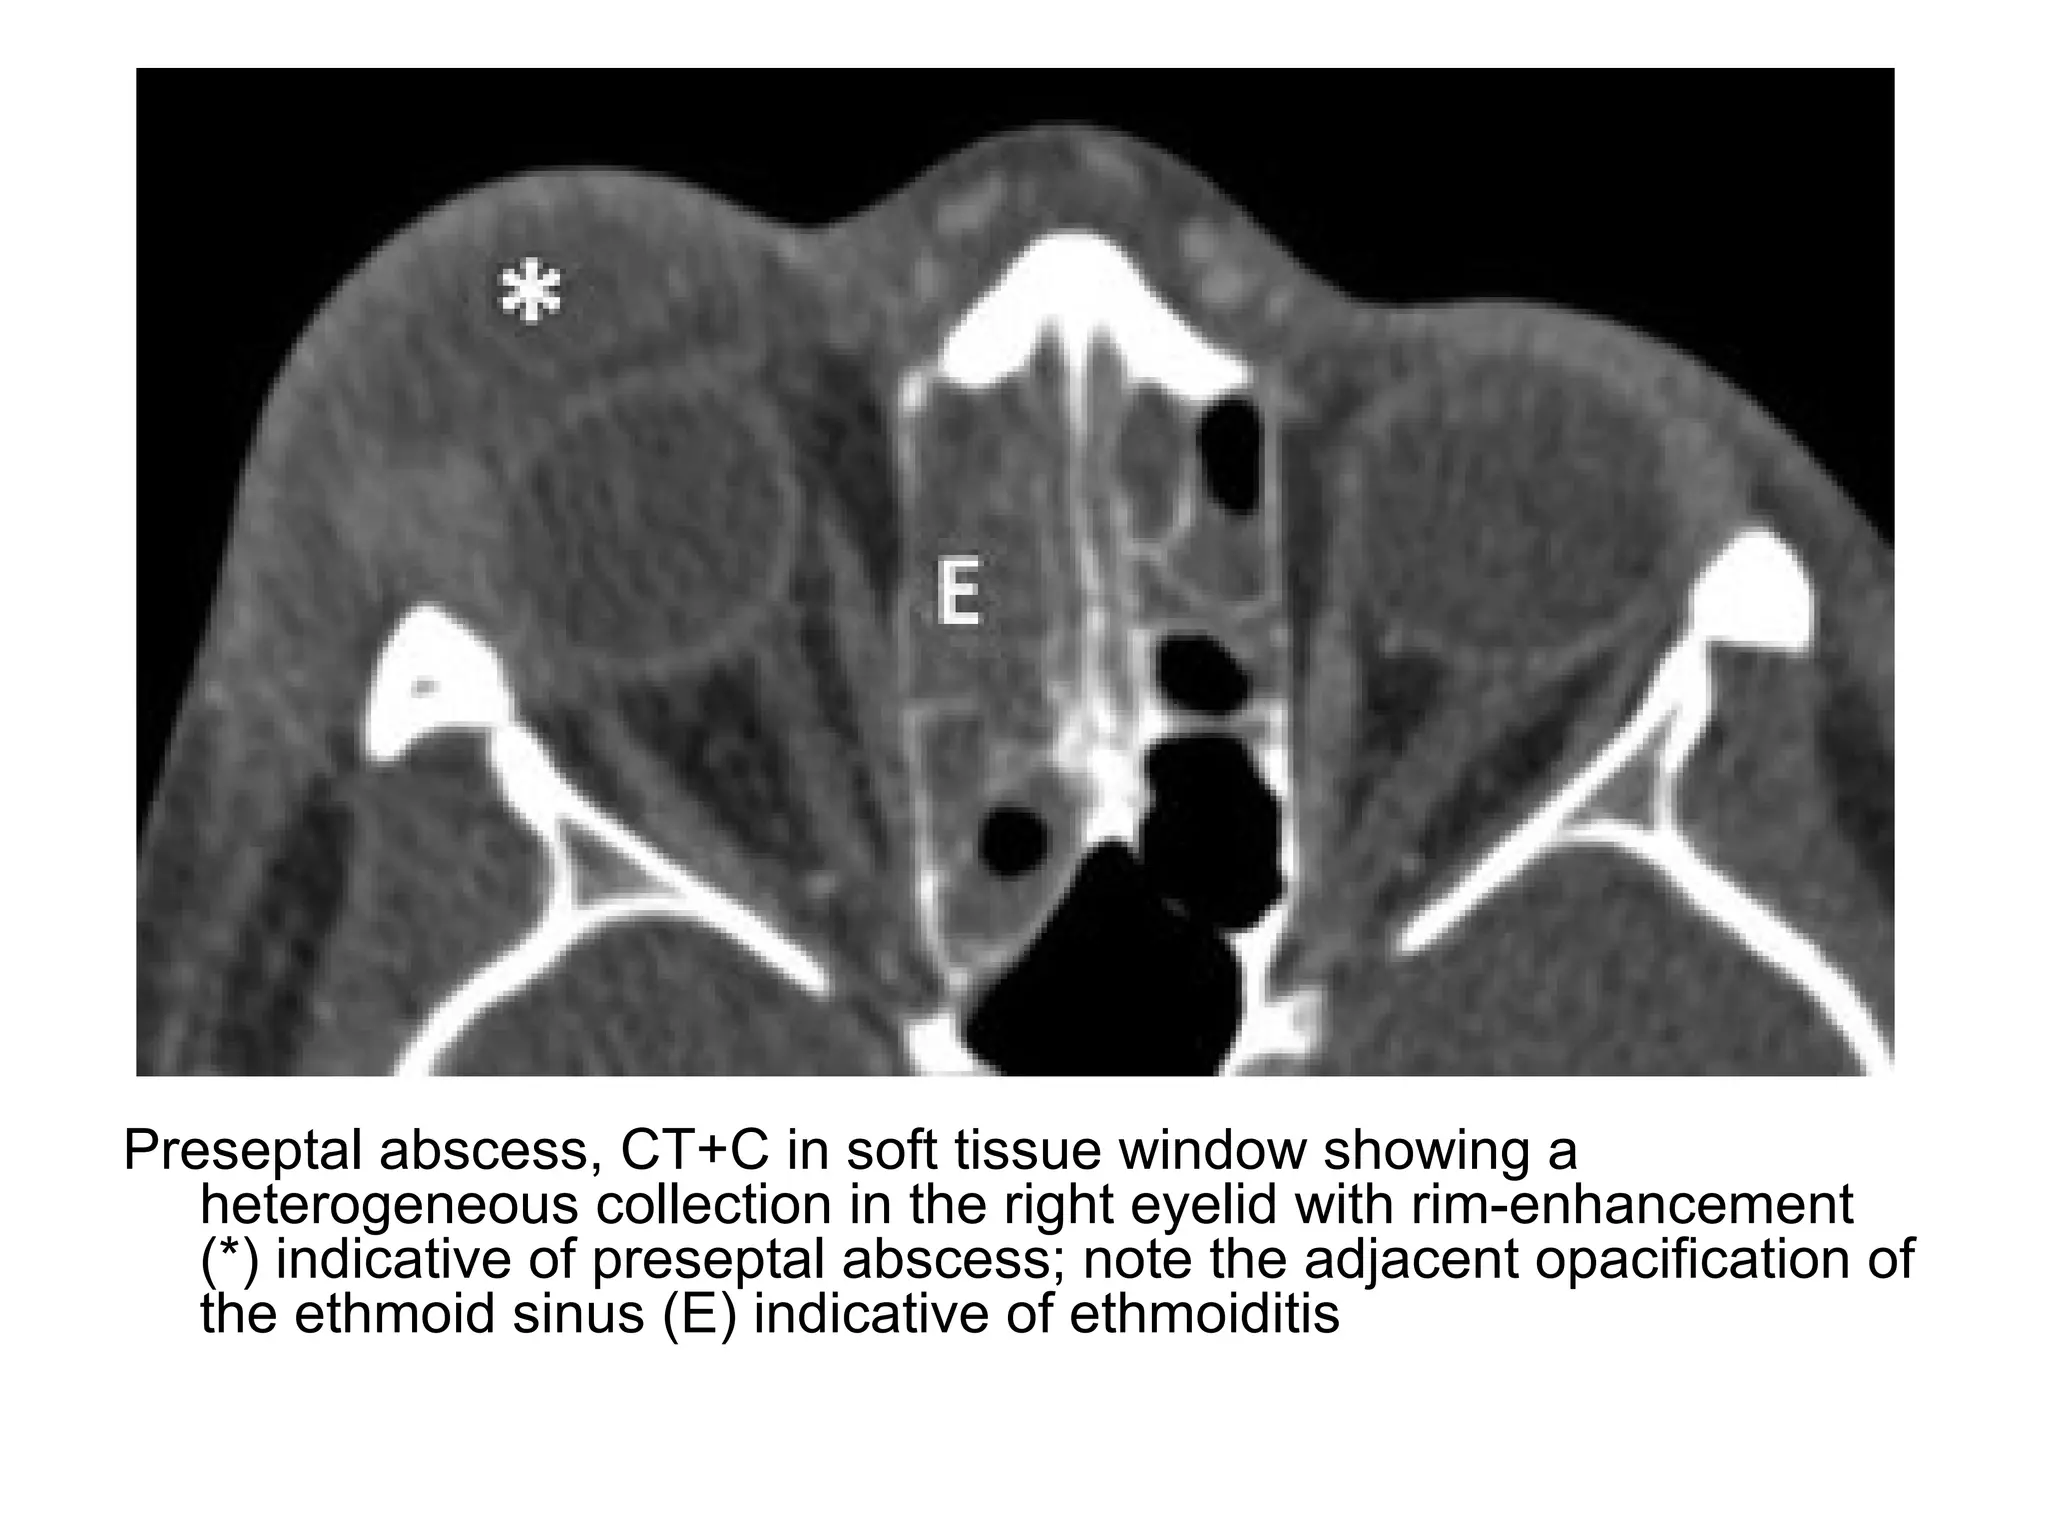

Preseptal abscess, CT+C in soft tissue window showing a

heterogeneous collection in the right eyelid with rim-enhancement

(*) indicative of preseptal abscess; note the adjacent opacification of

the ethmoid sinus (E) indicative of ethmoiditis